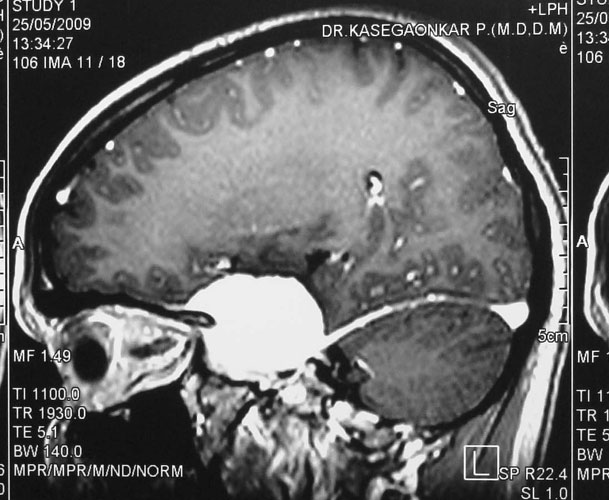

Medulloblastomas

Medulloblastomas are common tumors in childhood, often presenting with vomiting and headache. These tumors are located in midline of the cerebellum (back of the head). Diagnosis is made with MRI, and complete excision can be done safely in majority of the children.